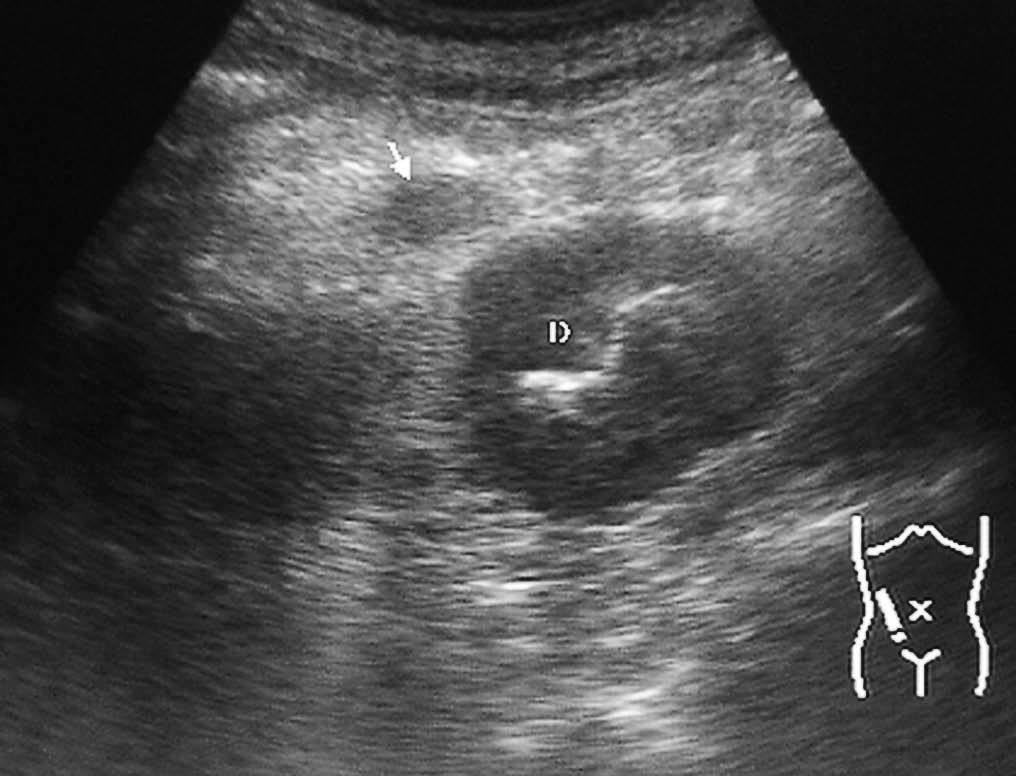

La enfermedad de Crohn afecta al duodeno de forma variable, apareciendo signos radiológicos en un 4% de los pacientes. Se manifiesta como un engrosamiento concéntrico y homogéneo de la pared, que puede producir estenosis de la luz intestinal (fig. 8). La existencia de actividad inflamatoria se identifica ecográficamente como aumento de la vascularización con modo doppler color. En la TC se observa la captación de la pared duodenal con afectación de la grasa adyacente.

Fig. 8--Enfermedad de Crohn duodenal. Corte ecográfico transversal donde se observa un engrosamiento concéntrico de la pared duodenal (D), que respeta la estructura de capas. VCI: Vena cava inferior; AO:aorta.